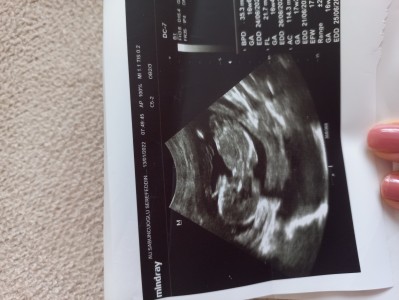

image  sizce  cinsiyet

nedir  kızlar ve bebeğimin 10   gün küçükmüş

Gebelik haftası ,, 17+6

Sırtı dönük belli olmuyor. Doktor görünce söyler zaten. Biraz daha büyüyünce bir özel doktora batırın derim

Arkası dönük belli olmuyor ama narin Bi yapısı var kız olabilr:)

Neden bilmem ama bana erkek geldi kızda bu haftada belirgin olmuyor bebeğin net çıkmış sırtı dönük